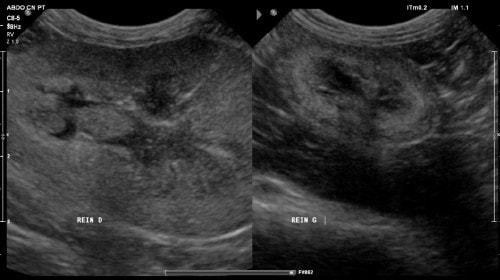

Une radiographie du rachis dorsal est conseillée mais refusée. Une échographie abdominale révèle des images compatibles avec une néphropathie bilatérale chronique avec asymétrie rénale marquée :

- atrophie rénale gauche et hypertrophie rénale droite (responsable de l’effet masse à la palpation abdominale) pouvant être compensatrice, associée à la présence d’éléments hyperéchogène non obstructifs dans les cavités pyéliques (cf. photos 5 et 6).

Photo 5 : cliché échographique montrant l’asymétrie rénale avec néphromégalie à droite et atrophie à gauche

Photo 6 : cliché échographique du rein droit montrant un élément hyperéchogène non obstructif dans la cavité pyélique avec cône d’ombre, compatible avec une urolithiase.

- pyélectasie bilatérale plus marquée à droite, compatible avec un phénomène sub-obstructif (calcul urétral, sténose), sans dilatation urétérale significative.